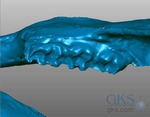

Objet Organizes a Dental System

3D printer manufacturer Objet has joined dental scanning provider 3Shape to create an integrated workflow solution specifically for dental restorations. The solution links 3D models produced by 3Shape’s dentist-focused scanning equipment and software directly into Objet’s Eden 3D printers. According to Avi Cohen, Head of Medical Solutions at Objet Geometries, the solution: includes special… Continue reading Objet Organizes a Dental System